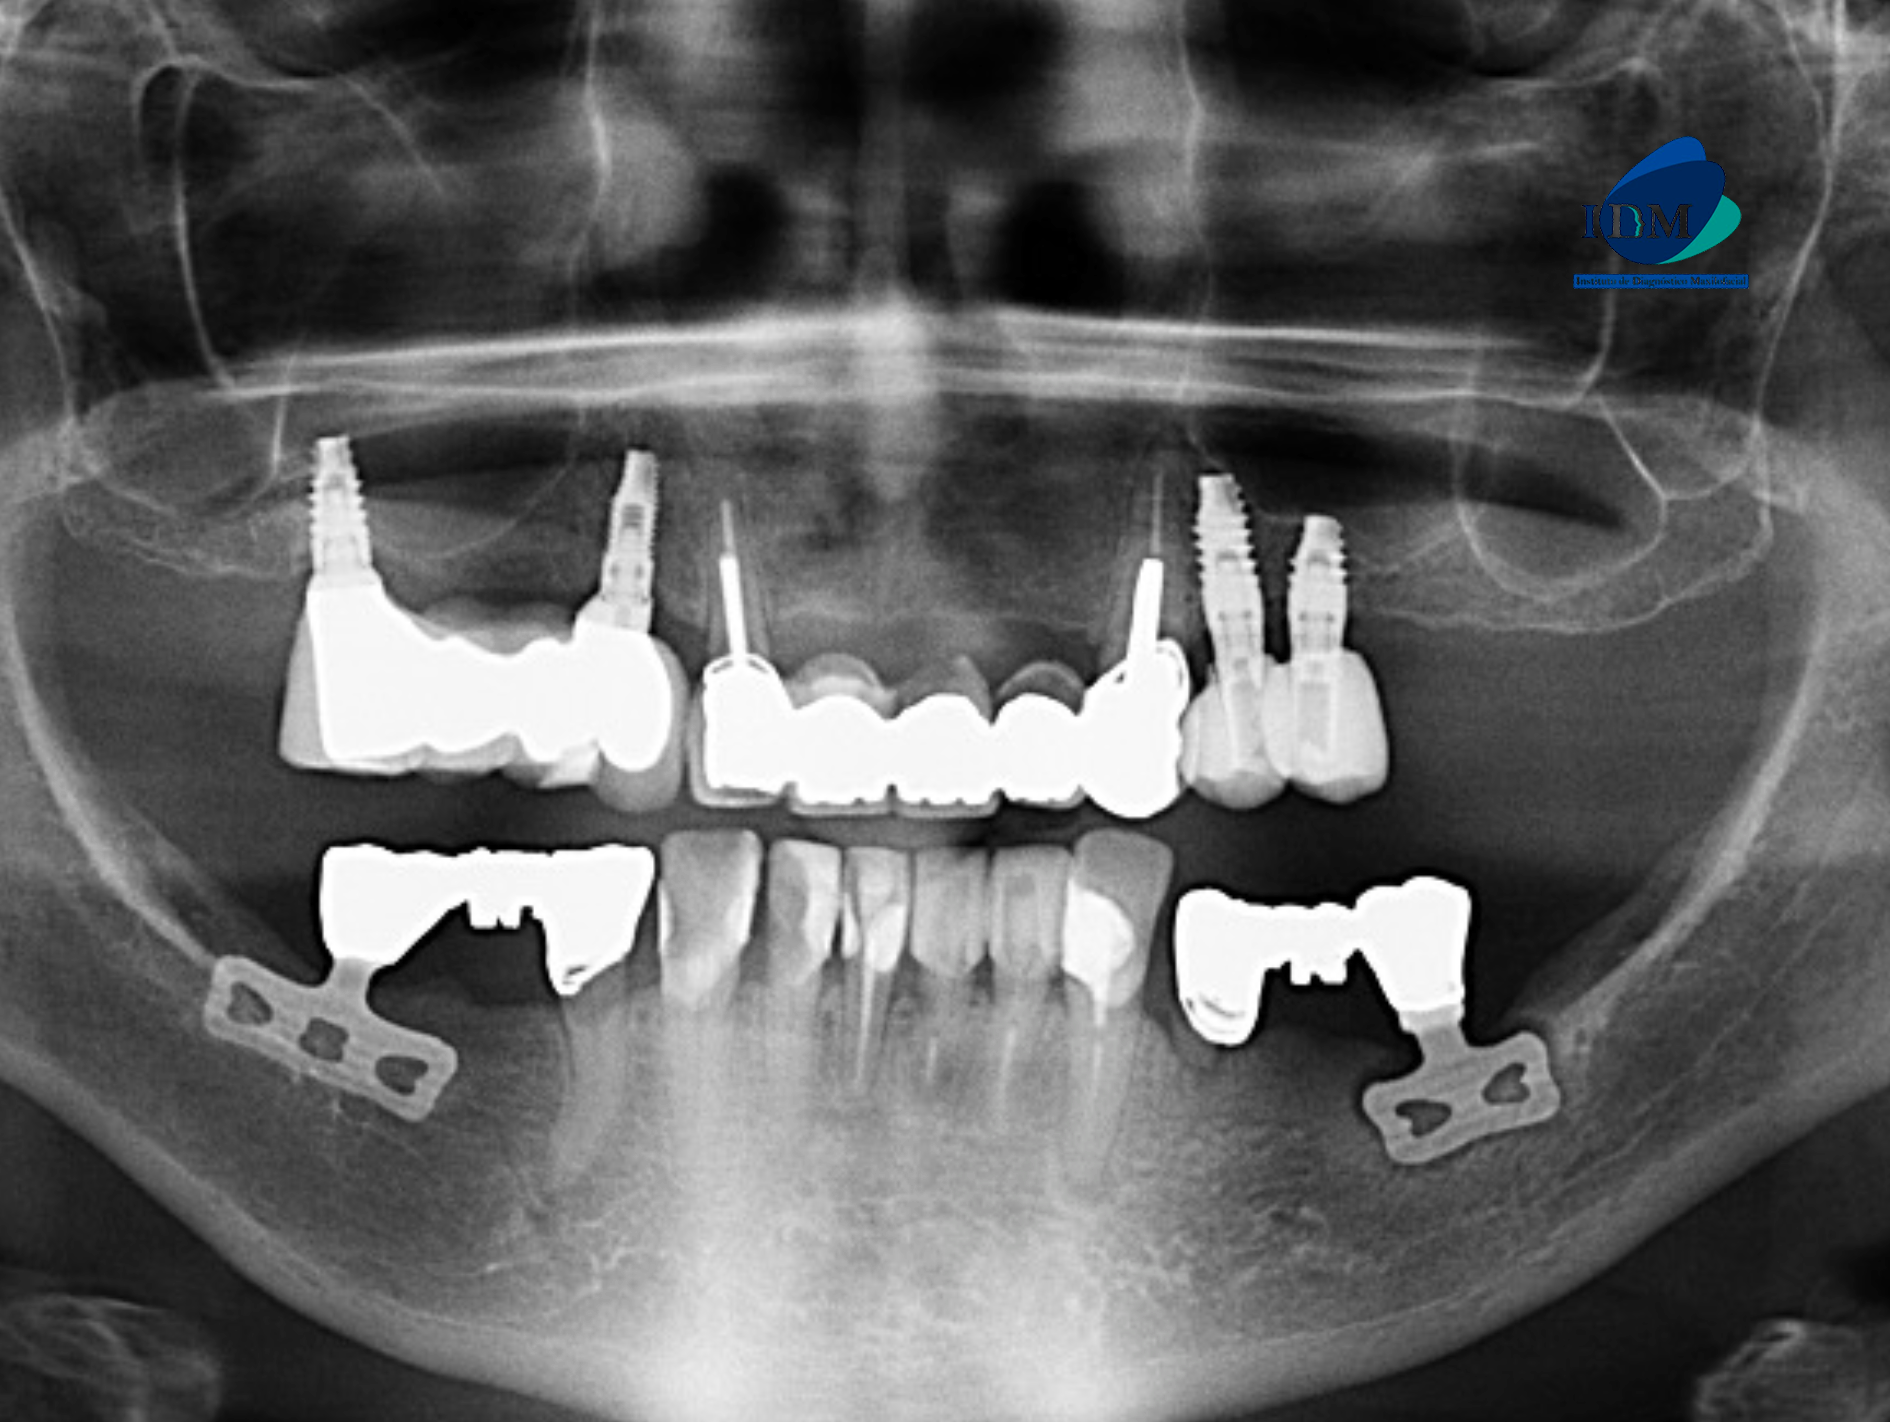

PACIENTE FEMENINO de 81 años acude al Instituto de Diagnóstico Maxilofacial PARA UNA TOMOGRAFÍA para colocación de implantes. A la evaluación de la radiografía panorámica se observa aplanamiento de ambos los contornos condilares, neumatización alveolar de ambos senos maxilares, múltiples piezas con obturación de conductos y coronas protésica, así como la presencia de implantes dentales en el maxilar superior proyectados sobre el piso de seno maxilar, también se observa proceso osteolítico periapical en la pieza 33 y finalmente se observa dos dispositivos metálicos proyectadas en zona de las piezas 36 y 46 compatibles con implantes dentales.

Radiografia Panorámica

Al observar la tomografía computarizada de campo mediano se puede observar que los implantes en el maxilar inferior son efectivamente de tipo laminares o de lámina perforada, además se puede observar en vistas axiales la presencia de una imagen hipodensa circundante al implante de zona de pieza 36 (flecha azul), en vistas transaxiales y tangenciales se evidencian pérdida de continuidad de tejido óseo en tercio cervical; características que no presenta el implante en zona de pieza 46 (flecha amarilla- vista axial). Signos imagenológicos compatible con perimplantitis.